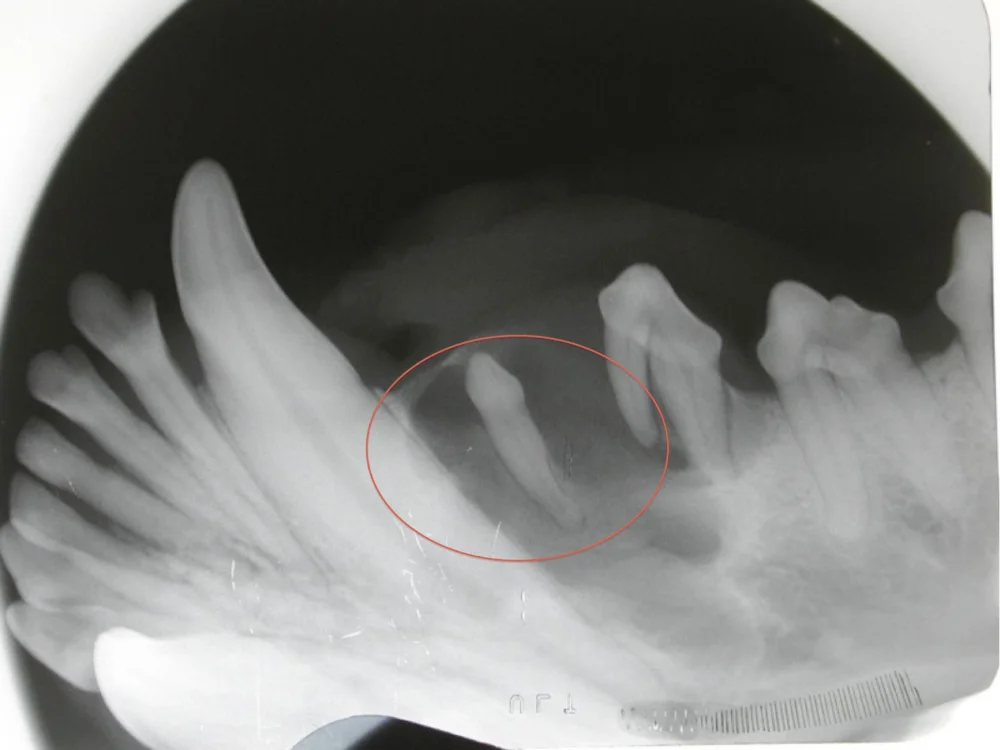

A swelling of the lower jaw was noted on a dog. On examination, no visible tooth in the area was noted. However, dental x-rays show a tooth below the gumline that was unerupted and had caused a cyst to form.